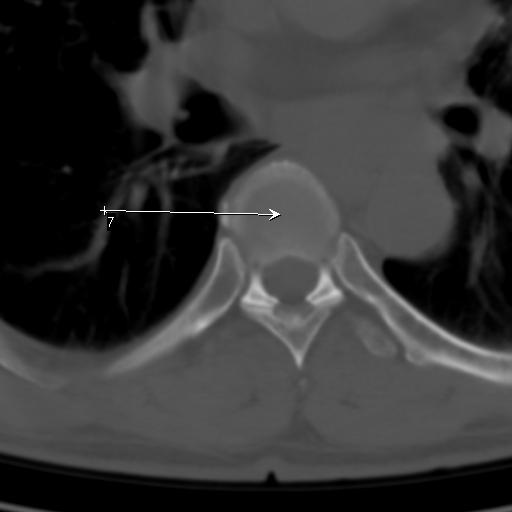

标题: CT25189:胸椎ct,请会诊!

既往食管癌,现行ct检查!

中上段食道癌,椎体轻度退变。

支持中上段食道癌,椎体轻度退变,必要时做ect。